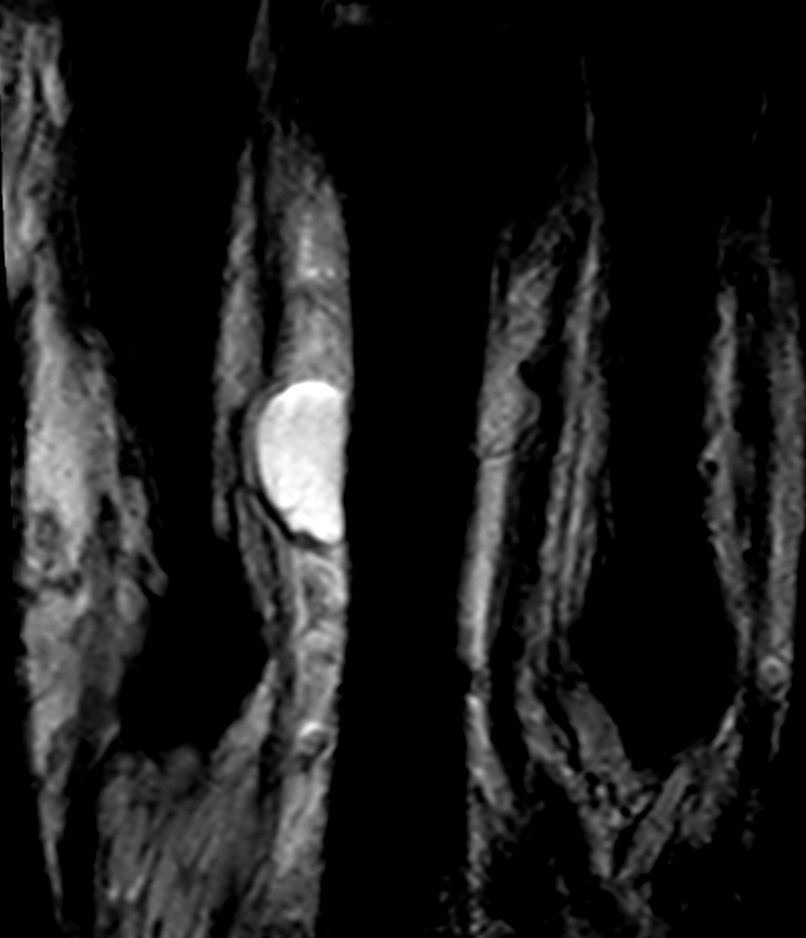

Patient with a ganglion in his finger. dS Microscopy coil set is used, consisting of two 47 mm coils, for small field-of-view imaging with high in-slice spatial resolution and a high signal-to-noise ratio. Compressed SENSE is used in all sequences to shorten the overall exam time for the patient.

Coronal T1w TSECompressed SENSE